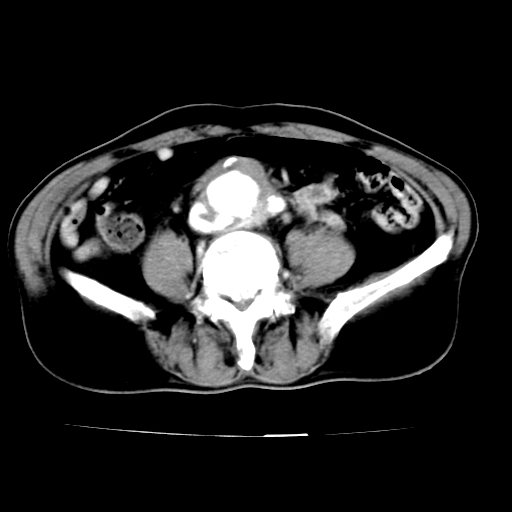

标题: V0243:右髂总动脉瘤附壁血栓形成?破裂?动静脉瘘? [打印本页]

标题: V0243:右髂总动脉瘤附壁血栓形成?破裂?动静脉瘘?

男,75岁,腹痛月余,彩超发现脐周腹主动脉异常回声。临床诊断:腹主动脉瘤。

ct诊断:右骼总动脉囊性动脉瘤并瘤内附壁血栓形成,与下腔静脉之间形成动静脉瘘。

请问各位老师:能排除动脉瘤破裂的可能吗?

各位老师注意到下腔静脉的充盈缺损了吗?注意到动静脉漏了吗?

当时是扫描的标准动脉期,可是下腔静脉与腹主动脉同步强化且幅度一致。所以我想动静脉瘘是存在的。